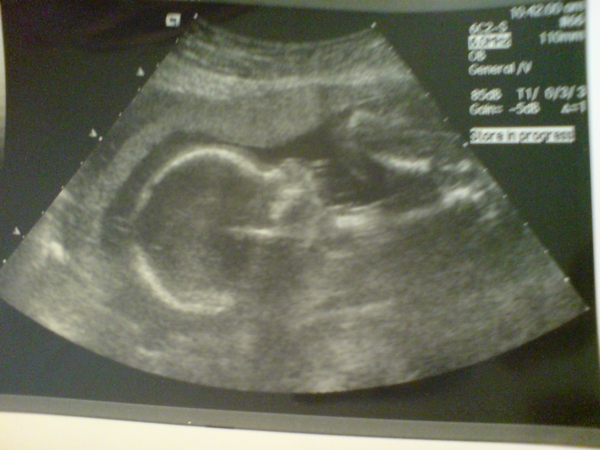

Będzie drugi synek:) Dzidzia zdrowa, i zrobią mi cesarkę jak będe chciała.

To Karolek

65528.JPG

No MEDIO- GRATULACJE!!! I juz imie tez masz. Dobrze, ze wszystko z dzieckiem w porzadku- to najwazniejsze.Fajniutkie zdiecie. I dobrze ze nie bedzie problemu z cesarka. Pozdrawiamy goraco...:-)